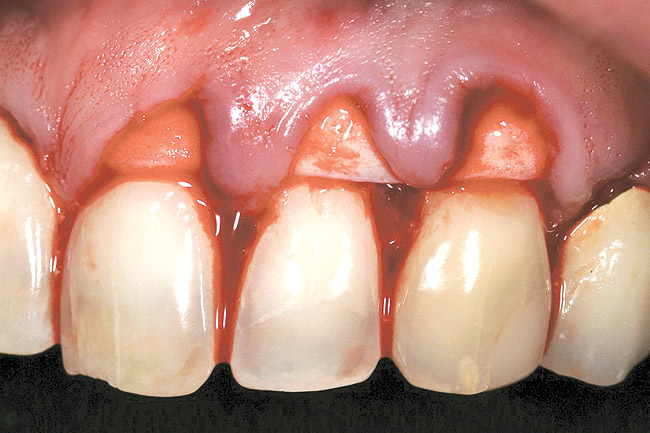

A 54-year-old non-smoking woman presented for correction of deep-wide gingival recession in the maxillary anterior (Figure 1 through Figure 3). The patient’s desires were to correct the gingival recession, balance the heights of contour of the tissues, and possibly undergo esthetic enhancement of the maxillary anterior with veneer restorations.

Figure 1  Case One Pretreatment clinical view, Case 1, maxillary right.

Figure 1

Figure 2  Case One Pretreatment clinical view, Case 1, maxillary anterior.

Figure 2

Figure 3  Case One Pretreatment clinical view, Case 1, maxillary left.

Figure 3